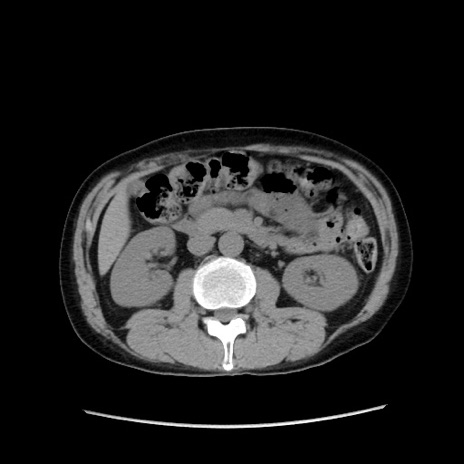

症例37(横断像)

【症例】40歳代 男性

【主訴】腹痛

【現病歴】4時間ほど前に電車に乗車中に臍部上より腹痛出現。徐々に増悪し起立困難となり、救急外来受診。生ものは数日食べていない。今朝お雑煮を食べた。

【身体所見】BT 36.8℃、BP 117/84mmHg、HR 91/min、SpO2 97%、苦悶様、腹部:臍上部広範囲圧痛あり、反跳痛±

【データ】WBC 8100、CRP 0.03